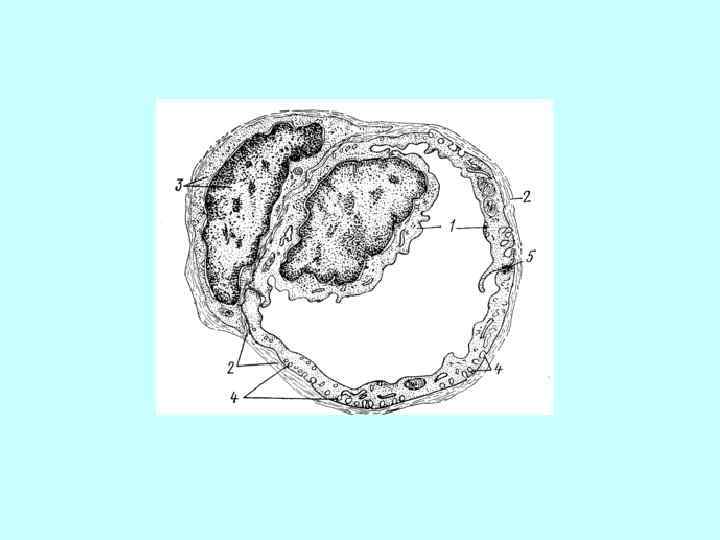

Проводящие миоциты в желудочке сердца Эндокард и в нём: • эндотелий; • субэндотелиальный слой; Проводящие миоциты в желудочке сердца Эндокард и в нём: • эндотелий; • субэндотелиальный слой; • мышечно-эластический слой; • субэндокардиальная основа Миокард: • проводящие миоциты; • рабочие миоциты.